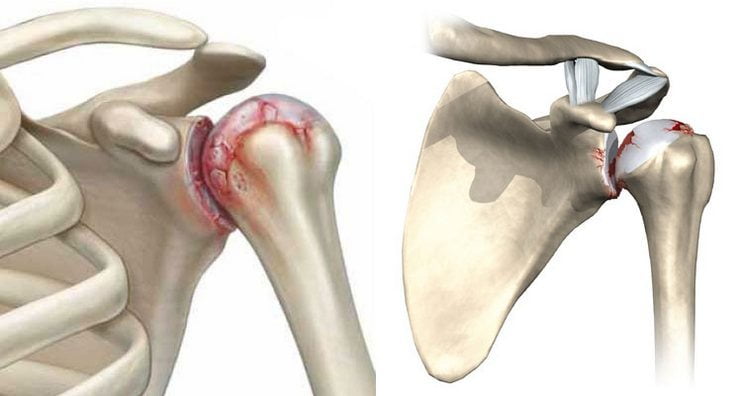

Артроз плечевого сустава — дегенеративно-дистрофическая патология, для которой характерно разрушение хрящей с последующей деформацией костных структур. Заболевание развивается из-за повышенных физических нагрузок, малоподвижного образа жизни, врожденных или приобретенных аномалий строения сочленения.

Спровоцировать артроз могут аутоиммунные патологии, например, системная красная волчанка, анкилозирующий спондилоартроз, ревматоидный артрит. Клинически заболевание проявляется следующими симптомами:

- болью в состоянии покоя, при сгибании и разгибании сустава, отведении и подъеме руки;

- утренней припухлостью и скованностью движений;

- хрустом, щелчками, треском, возникающими при любом движении плечом.

Если больной не обращается за медицинской помощью, то наблюдается снижение мышечной силы и чувствительности, выпадение рефлексов. Постепенно сращивается суставная щель, что приводит к полному или частичному обездвиживанию (анкилозу).